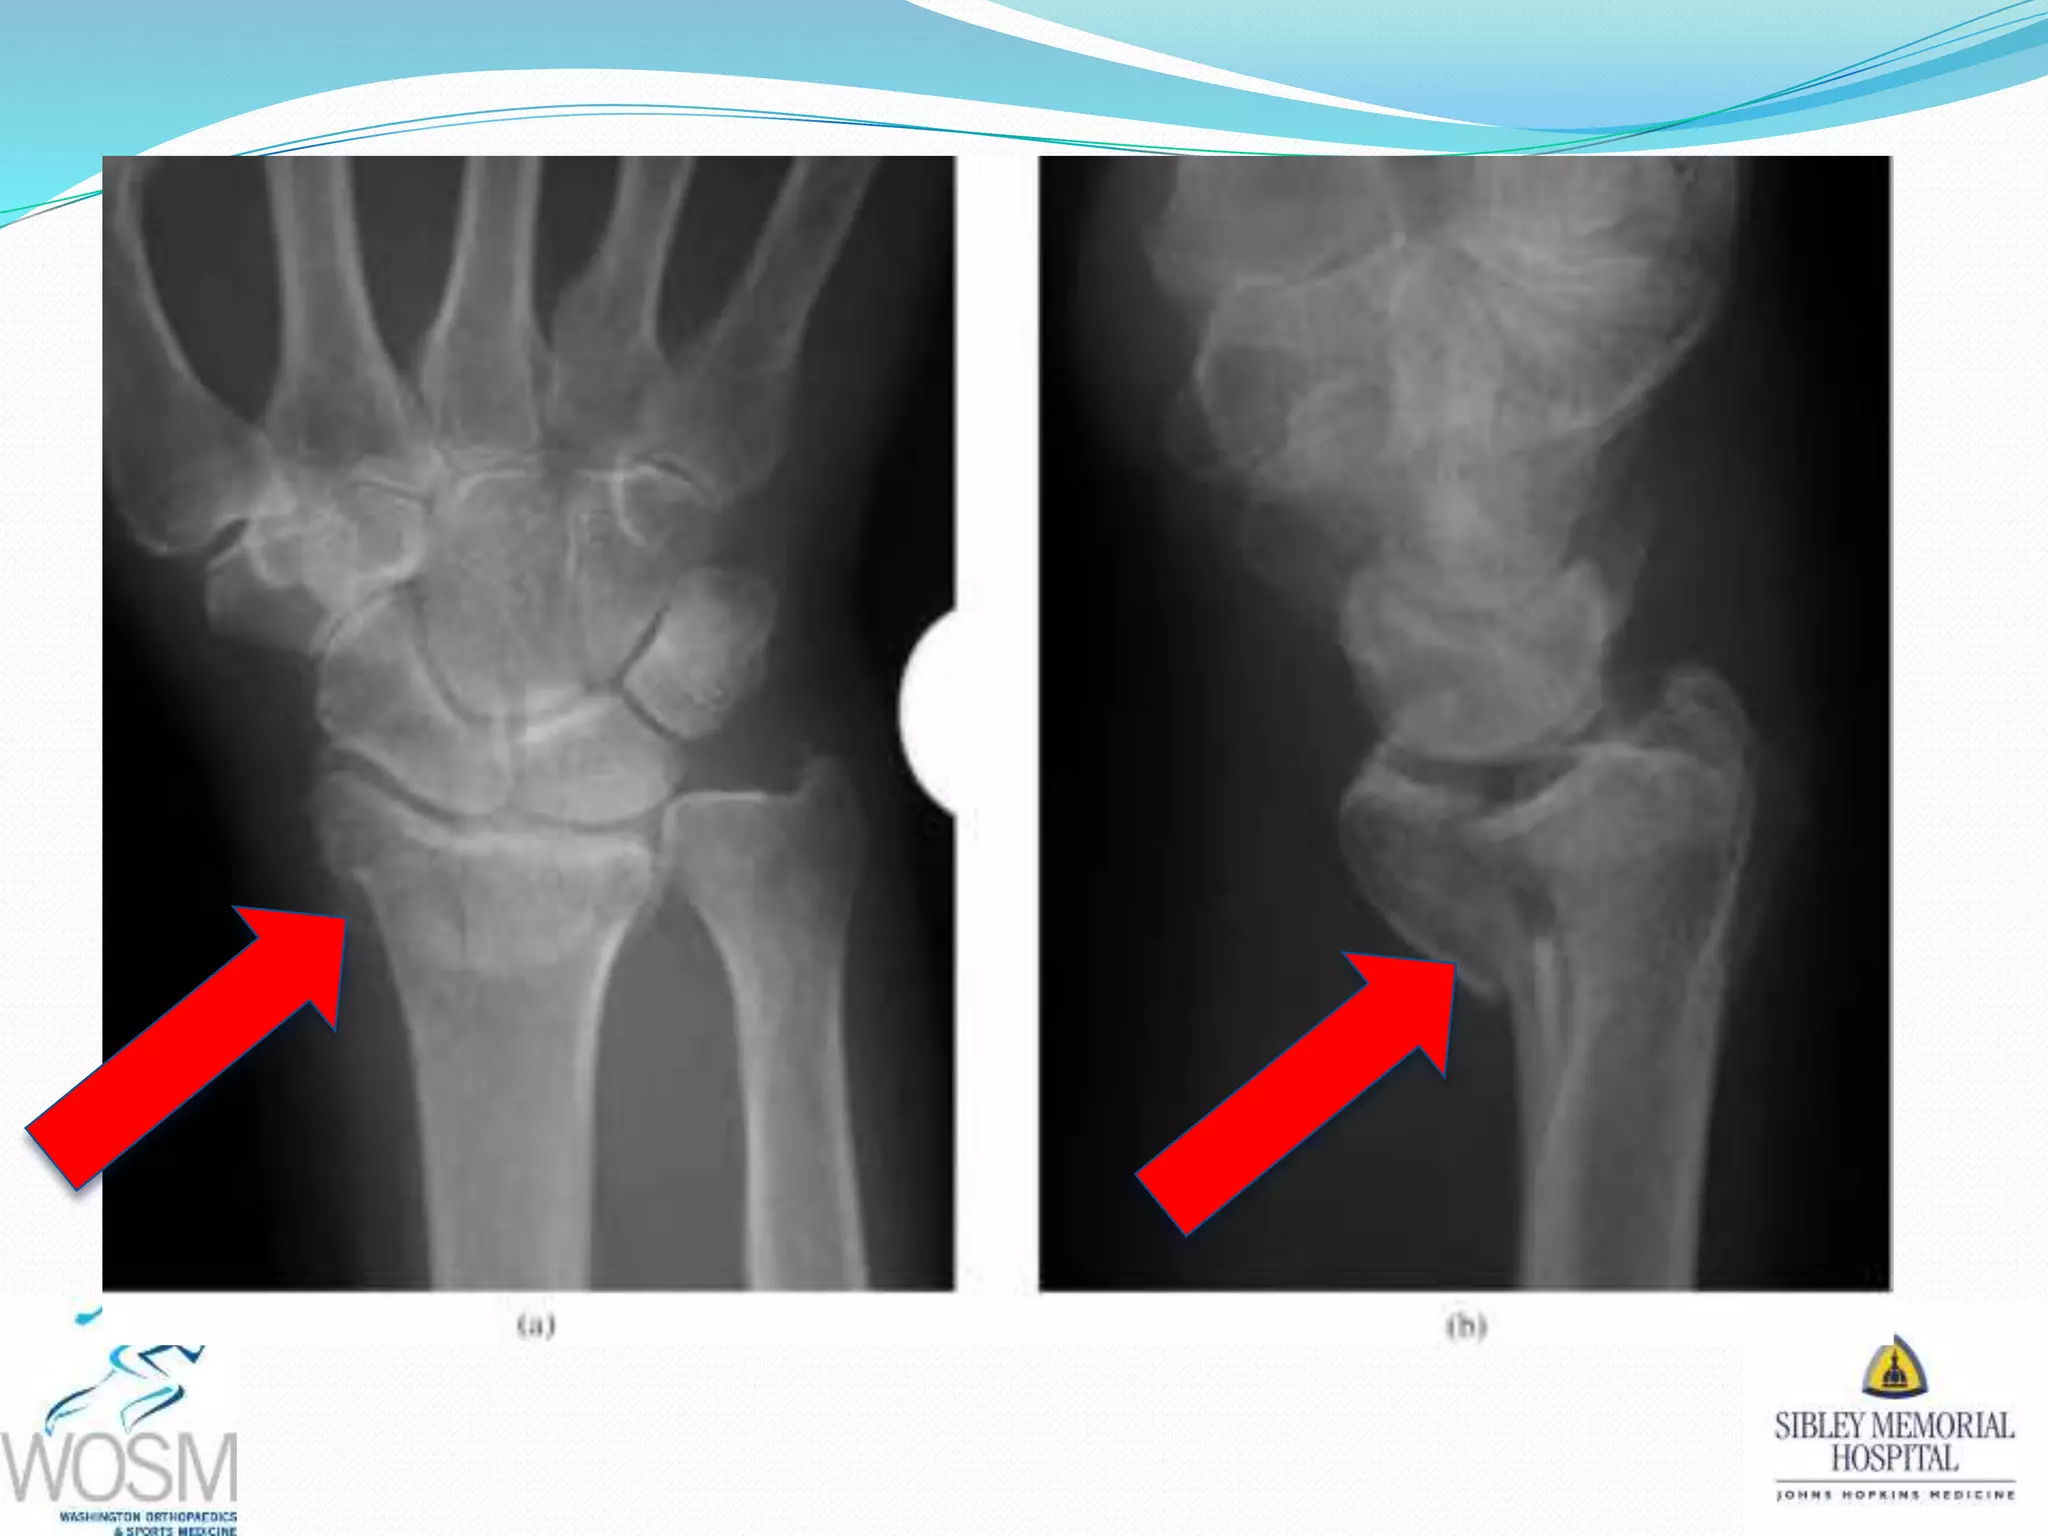

This document discusses wrist fractures, including who is most at risk, common causes, signs and symptoms, treatment options, and prevention. The elderly and those with osteoporosis are most prone to wrist fractures due to falls. Treatment may involve splinting, casting, closed reduction, or surgery depending on the fracture. Maintaining bone health through medication, vitamins, exercise, and diet can help prevent wrist fractures.